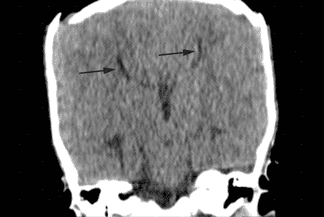

Descrição da imagem: A reconstrução no plano coronal demonstra a ausência do corpo caloso e os ventrículos laterais separados (aparência de "cabeça de búfalo" - setas pretas).

Exames de imagem: Melhor pista diagnóstica é a ausência parcial ou completa do corpo caloso na linha média dos planos sagital ou coronal + ventrículos laterais separados e paralelos (axial), aparência de "cabeça de búfalo" ou "cabeça de alce".